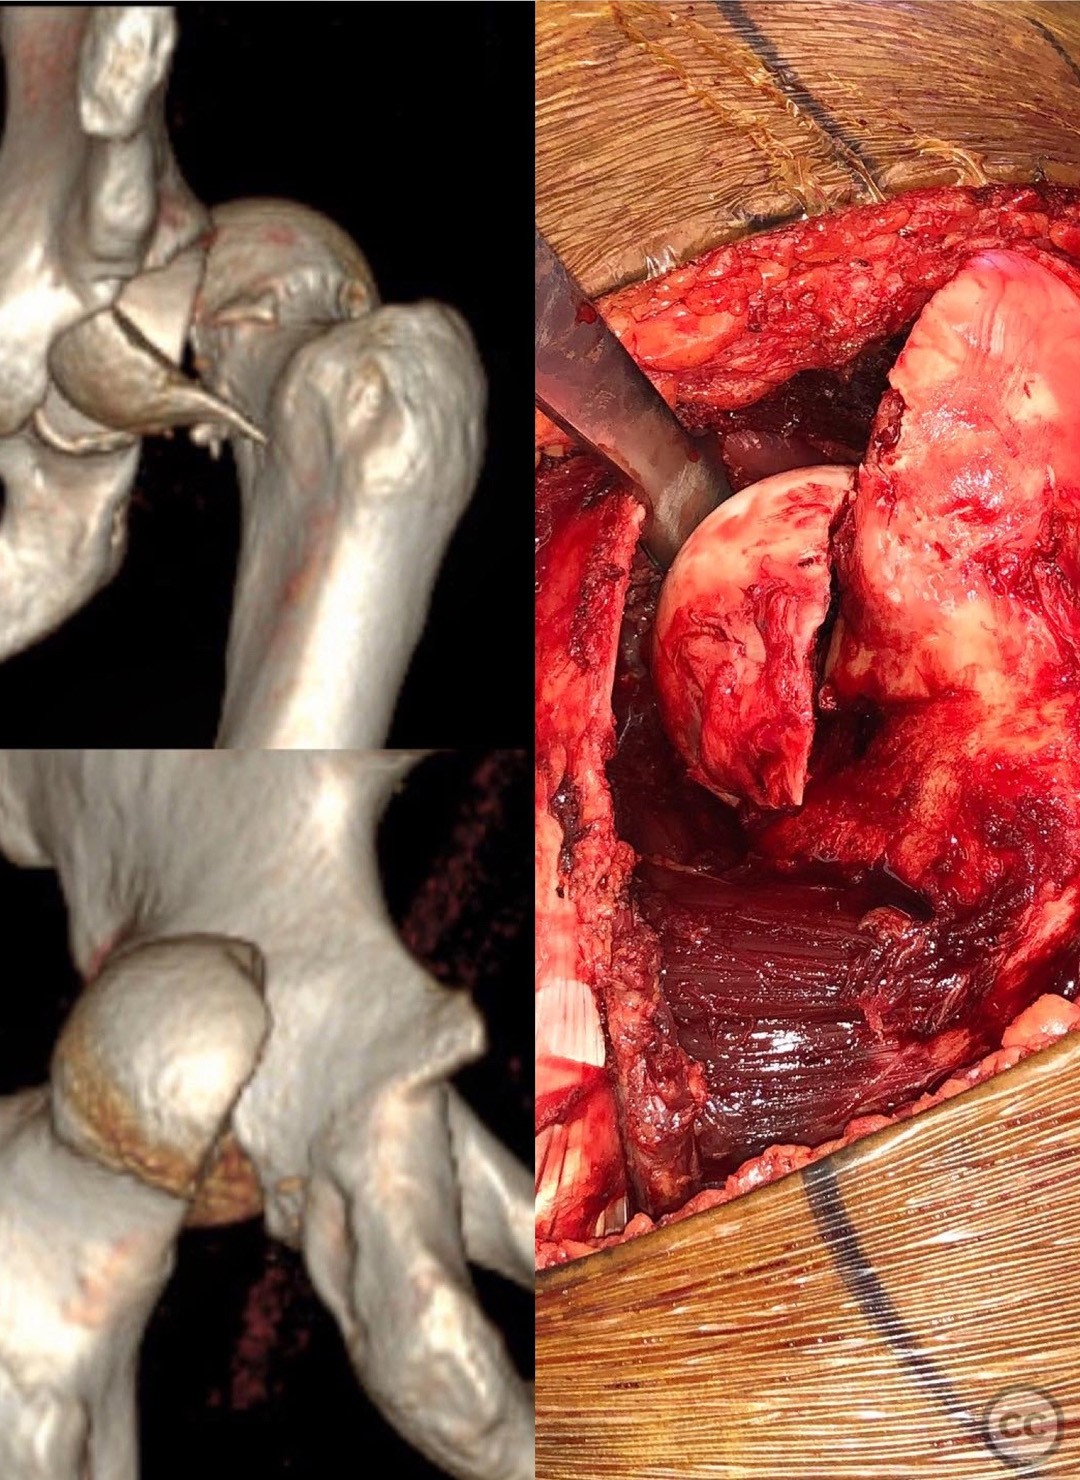

Pipkin IV Femoral Head Fracture with Ace...

Seattle, United States

Femur - AO/OTA 3x

Pipkin IV Femoral Head Fracture Dislocat...

Pipkin IV Femoral Head Fracture with Fem...

Pipkin Type III Femoral Head and Neck Fr...

Pipkin 2 + cranial peripheral acetabular...